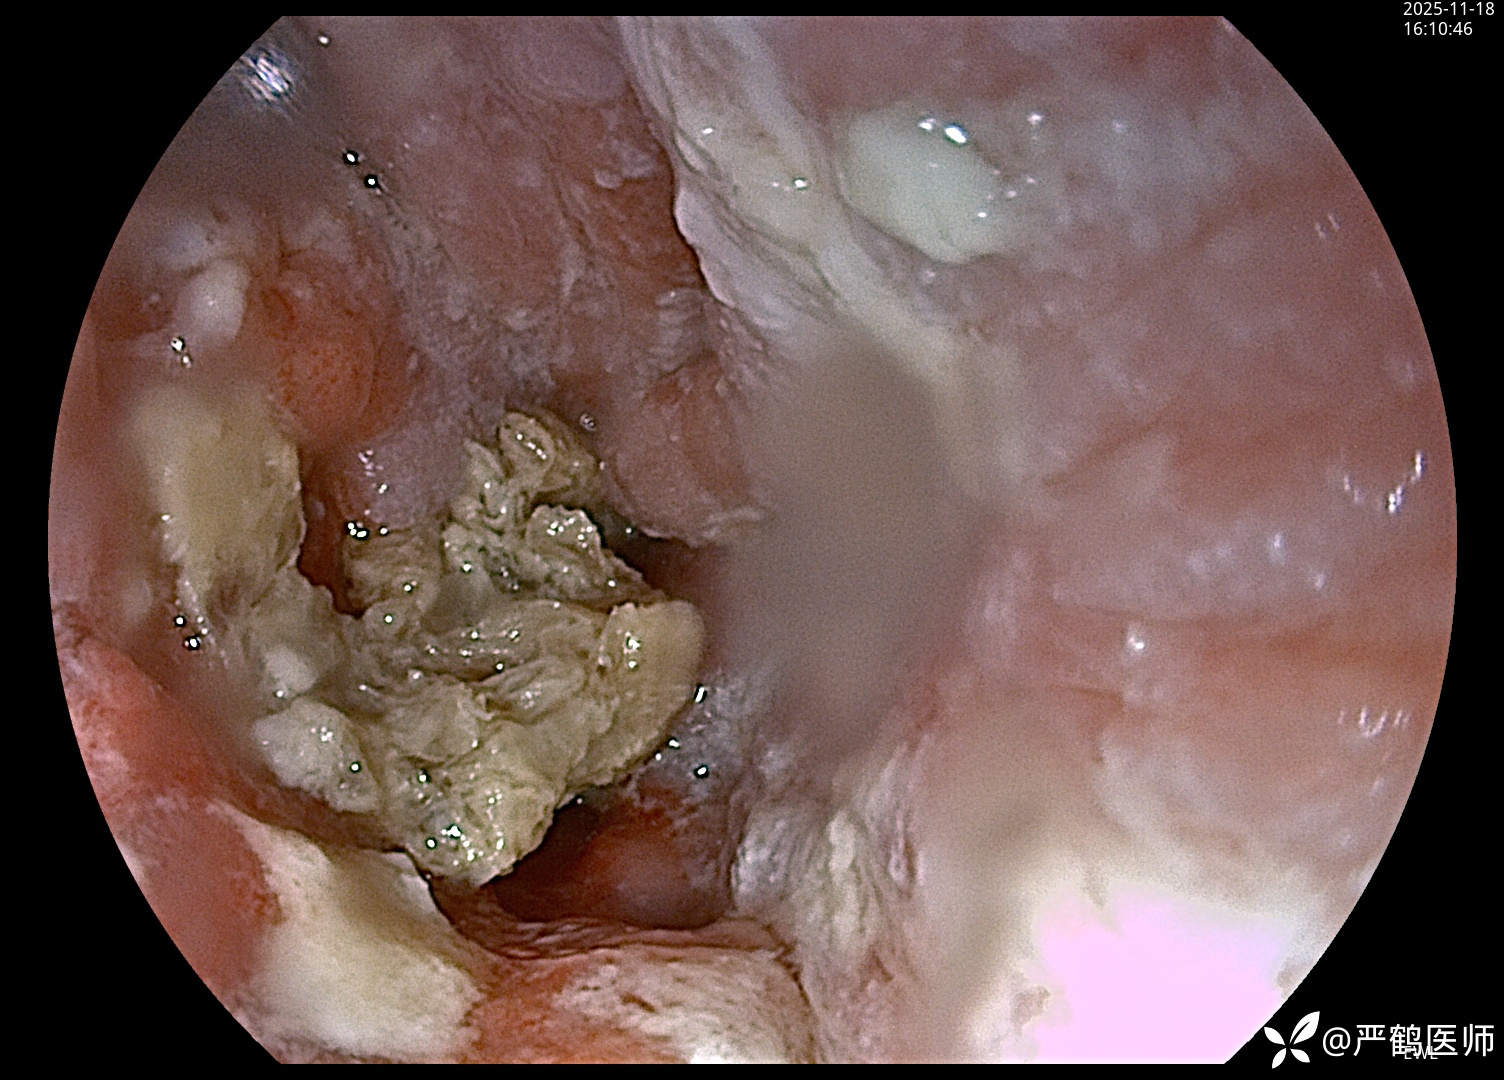

食管癌覆膜支架置入术

老年男性,食管距门齿30cm处肿瘤至进食梗阻,无法手术,家属不愿进一步行放化疗治疗,置入全覆膜食管支架解除梗阻,缓解进食困难症状